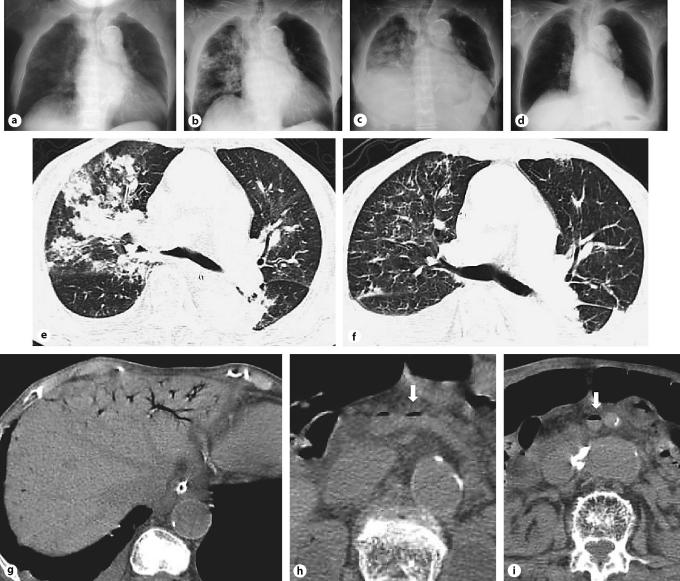

We describe a case of pulmonary gas embolism caused by portal vein gas (PVG) observed using echocardiography. Echography revealed gas flowing through the hepatic vein, inferior vena cava, right atrium, and right ventricle, as well as pulmonary hypertension. The patient was diagnosed as having pulmonary gas embolism caused by PVG.

Mortality of gas embolism caused by PVG was 67%, positive blood culture was observed in six cases, and pulmonary edema was seen in three cases. PVG initially excites microbubble formation, which causes tissue damage in the liver and liver abscess. A large volume of PVG causes portal obstruction. As a result, portal hypertension, a portosystemic shunt or gastrointestinal congestion can occur. PVG can travel to the systemic vein through the liver or portosystemic shunt without anomaly and cause pulmonary gas embolism, followed by arterial embolism. In this environment, sepsis easily occurs. Echocardiography is useful for diagnosis of gas embolism caused by PVG, but the gas can be seen intermittently. The view of pulmonary edema is important for pulmonary gas embolism caused by PVG.

我们描述了一例通过超声心动图观察到的由门静脉气体(PVG)引起的肺气体栓塞病例。超声检查显示气体流经肝静脉、下腔静脉、右心房和右心室,同时伴有肺动脉高压。该患者被诊断为由PVG引起的肺气体栓塞。

由PVG引起的气体栓塞死亡率为67%,6例血培养呈阳性,3例出现肺水肿。PVG最初会激发微泡形成,导致肝脏组织损伤和肝脓肿。大量的PVG会导致门静脉阻塞。结果,可能会发生门静脉高压、门体分流或胃肠道充血。PVG可通过肝脏或门体分流无异常地进入体循环静脉,引起肺气体栓塞,随后导致动脉栓塞。在这种情况下,败血症很容易发生。超声心动图对诊断由PVG引起的气体栓塞很有用,但气体可能会间歇性出现。肺水肿的表现对由PVG引起的肺气体栓塞很重要。